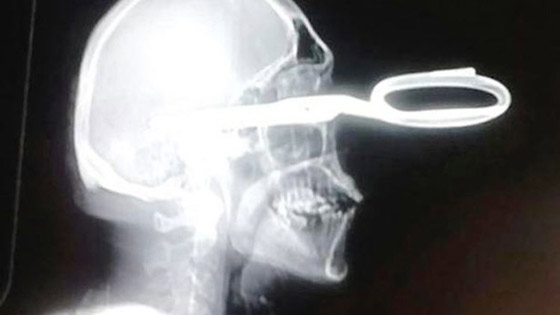

وُصِف رجل بالغ من العمر 32 عاما من أبناء مدينة تشواتشوا المكسيكية بأنه أكثر زبائن المستشفى المحلي تهذبا وهدوء. وكتبت صحيفة "ميرور" أن الرجل أتى الى المستشفى ماشيا على قدميه ومقص منغرز في رأسه، وليقول للطبيب أنه يواجه "مشكلة بسيطة".

وفي التفاصيل، قال شهود العيان إن الرجل كان جالسا في البار مع اصدقائه عندما اقترب منه شخص مجهول فبدأ في إهانته. وكان تصرف الرجل هادئا حيث حاول تحويل النزاع إلى مجرد مزح بسيط. لكن المجهول اشتد غضبا، فسحب مقصا من جيبه واعتدى على الرجل غارزا المقص في رأسه ، ثم فر من البار. ولحسن الحظ بقي الرجل على قيد الحياة لأن المقص لم يصب القسم الخلفي لدماغه. أما الشخص المعتدي فألقت الشرطة القبض عليه.